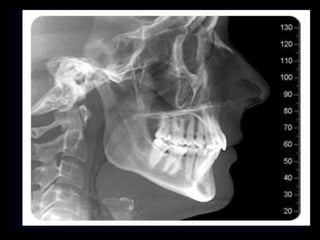

Telerradiografía

• Es una Radiografía extra bucal, se trata de una

radiografía tomada desde fuera de la boca y a

una distancia determinada.

• Las arcadas dentales están en el

intercuspidazion máximo

• Los labios tienen que ser guardados en la

posición natural